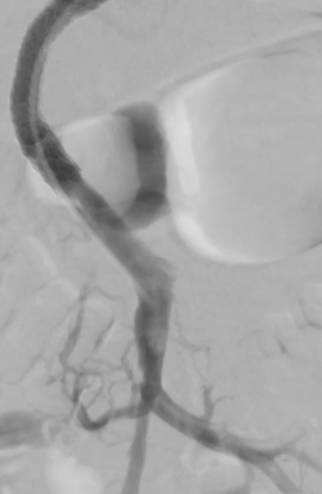

经右侧颈内静脉对肝内门静脉进行穿刺

将 VIATORR CX 型覆膜支架植入体内,以确保能够进入门静脉。 门静脉和肠系膜静脉的血栓清除术 肠系膜静脉中放置带有侧孔的溶栓导管,以处理残留的血栓物质